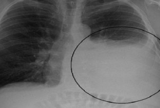

Akciğerde sıvı birikmesi olarak bilinen plevrale füzyon, kalp ve karaciğer yetmezliği gibi sistemik hastalıkların yanı sıra kanser ya da tüberküloz gibi lokal hastalıklarda da görü..